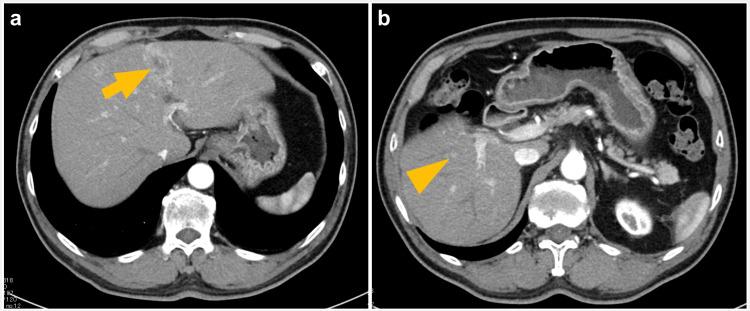

This was a retrospective study of nine patients with two to three hepatocellular carcinomas who had undergone laparoscopic HR combined with laparoscopic RFA between December 2014 and February 2022. Six patients tested positive for hepatitis C virus, two had alcoholic cirrhosis, and one had non-alcoholic steatohepatitis. All patients had a Child-Pugh score of 5 (A). All 22 lesions were treated as planned. Laparoscopic HR was performed on 12 and laparoscopic RFA was performed on 10 lesions. Postoperative hemorrhage occurred in one patient and was managed conservatively. The remaining eight patients were discharged without complications. Recurrence occurred in the residual liver in eight patients. However, no local recurrence at the treatment site was noted during the observation period (15-94 months).

这是一项对9例患有两至三枚肝细胞癌患者的回顾性研究,这些患者在2014年12月至2022年2月期间接受了腹腔镜HR联合腹腔镜RFA治疗。6例患者丙型肝炎病毒检测呈阳性,2例患有酒精性肝硬化,1例患有非酒精性脂肪性肝炎。所有患者的Child-Pugh评分为5分(A级)。所有22个病灶均按计划进行了治疗。12个病灶接受了腹腔镜HR治疗,10个病灶接受了腹腔镜RFA治疗。1例患者术后发生出血,经保守治疗。其余8例患者无并发症出院。8例患者在残余肝脏中出现复发。然而,在观察期(15 - 94个月)内未发现治疗部位有局部复发。